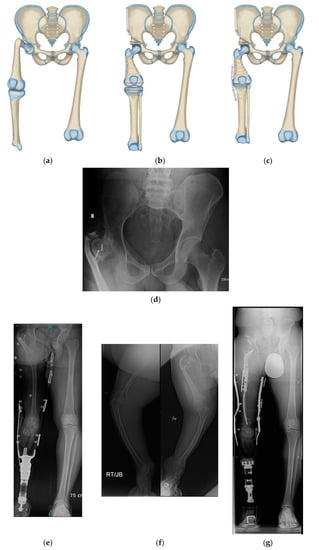

Figure 4.

(a) Paley rotationplasty illustration. (b) AP pelvis of 2-year-old boy with CFD Paley type 3a. (c) Standing radiographs in same boy before surgery showing ankle is at level of opposite knee. (d) Since the femoral head was mobile a Paley rotationplasty was performed. Standing long radiograph in same boy, 8 years after Paley rotationplasty. (e) To improve his prosthetic fitting he had a varus derotation surpramalleolar osteotomy performed 8 years after the original rotationplasty. Clinically he is very sports active and has excellent gait and function.

Figure 5.

(a) Illustration of CFD Paley type 3c. There is an ankylosed knee with a small distal femoral remnant. (b) Illustration showing the femoral head is enucleated to make room for the femoral condyle or tibial plateau in the acetabulum. (c) Paley–Winkelmann rotationplasty illustration, inserting the femoral condyle remnant into the acetabulum secured with a hip tethering suture. (d) AP pelvis radiograph of a 12-year-old girl with CFD Paley type 3c. (e) Standing long radiograph of same girl showing the ankle is at the level of the opposite knee. (f) AP pelvis radiograph of same girl after Paley–Winkelmann rotationplasty with femoral condyle in the acetabulum. The tethering suture anchor is seen. (g) Standing radiograph of same girl 5 years after Paley–Winkelmann rotationplasty. She has excellent function of the new hip joint and can walk and run with very minimal limp.